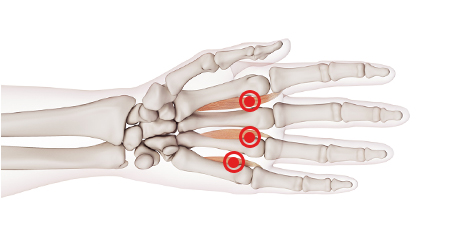

방아쇠수지 (손가락 힘줄염)

손가락을 굽히는 힘줄에 염증이 발생한 질환